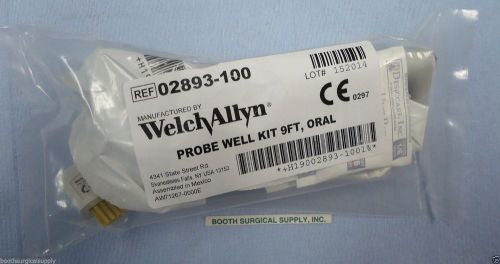

WELCH ALLYN # 02893-100 PROBE WELL KIT WITH 9' ORAL PROBE--NEW IN SEALED POUCH